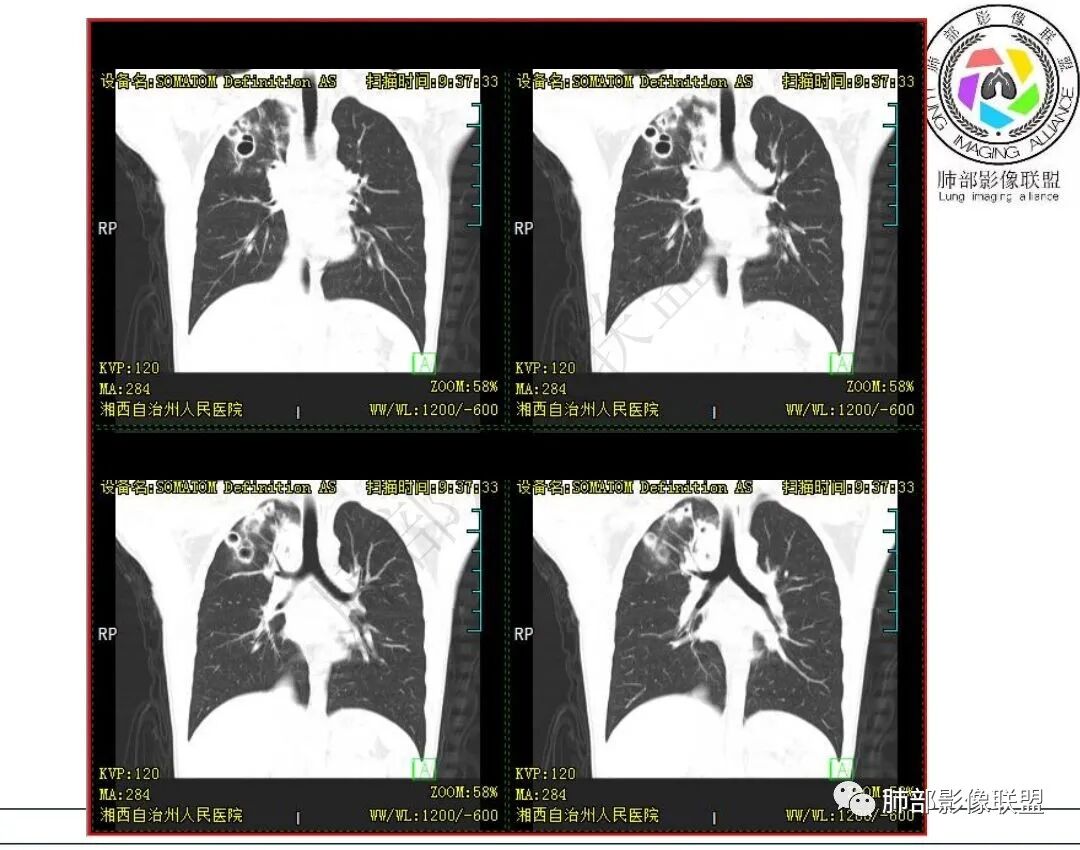

影像:右肺上叶多发实变影结节影,边界模糊,边缘收缩,伴多发空洞,洞壁光滑,部分支气管壁增厚。

3.首次CT提示:右肺上叶多发结节影及实变影,簇状分布,周围散在磨玻璃影,结节内多类圆形空洞,内壁光整,有一定张力,偶见液平。部分支气管壁增厚。

考虑良性感染性病变可能。

本例病灶分布特点比较偏中央分布,不是我们常见的隐球外围胸膜下。看来诊断隐球,分布不能太绝对,至少不能作为绝对排除项。